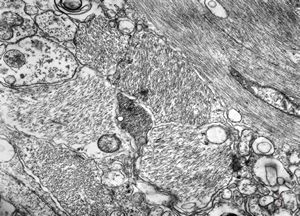

F,50y. | progressive multifocal leukoencephalopathy- viral particles in a glial cell

F,50y. | progressive multifocal leukoencephalopathy- viral particles in a glial cell

F,50y. | progressive multifocal leukoencephalopathy- viral particles in a glial cell